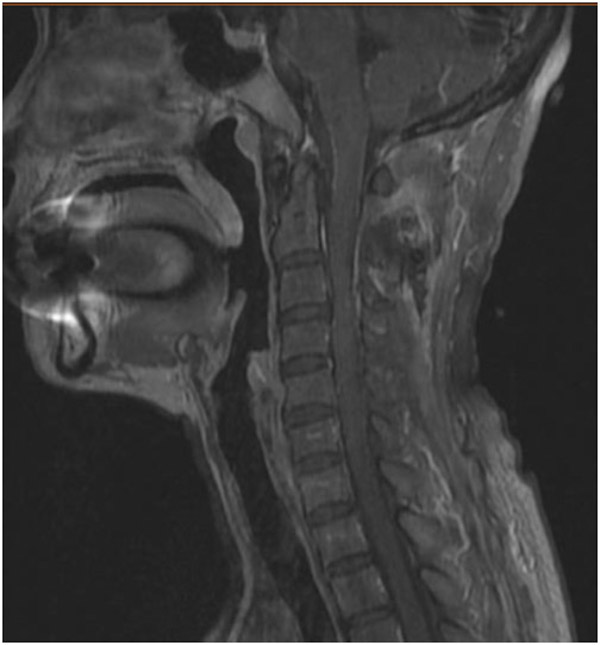

58歲的蘭女士因胸部束縛感2年,左上肢麻痛1年在當(dāng)?shù)蒯t(yī)院就診,經(jīng)檢查發(fā)現(xiàn)患者高位頸髓區(qū)域有一顆巨大腫瘤,手術(shù)風(fēng)險(xiǎn)大,術(shù)后出現(xiàn)高位截癱的可能性非常高。為求更好的治療方案,蘭女士輾轉(zhuǎn)了多家醫(yī)院,最終來(lái)到了柳州市人民醫(yī)院神經(jīng)外科。

了解到患者的病情后,神經(jīng)外科治療團(tuán)隊(duì)迅速作出了判斷:此類腫瘤常規(guī)手術(shù)要采用至少15cm以上長(zhǎng)切口切除,切除多節(jié)段椎板影響脊柱的穩(wěn)定性,需要行內(nèi)固定手術(shù),頸1、2內(nèi)固定將嚴(yán)重影響患者的頸部活動(dòng),為日后生活帶來(lái)諸多不便。

于是神經(jīng)外科治療團(tuán)隊(duì)便針對(duì)患者的特點(diǎn)制定了手術(shù)方案,采用改良側(cè)方肌間隙半椎板入路,僅需6cm手術(shù)切口,術(shù)中電生理監(jiān)測(cè)在顯微鏡+神經(jīng)內(nèi)鏡下全切腫瘤,這種方法可精準(zhǔn)的暴露頸髓側(cè)方及腹側(cè)的腫瘤,避免頸髓的牽拉,減少了手術(shù)創(chuàng)傷,縮短手術(shù)時(shí)間,后路絕大部分椎板、肌肉及韌帶保留,降低了患者術(shù)后椎柱失穩(wěn)的風(fēng)險(xiǎn),無(wú)需內(nèi)固定。

聽(tīng)了醫(yī)生的解釋后,蘭女士欣然決定進(jìn)行手術(shù)治療,困擾自己的2年多的病痛終于有了妥善的解決辦法。手術(shù)非常成功,術(shù)后癥狀便得到了緩解,2周后患者痊愈出院,目前頸部活動(dòng)自如,無(wú)任何后遺癥。